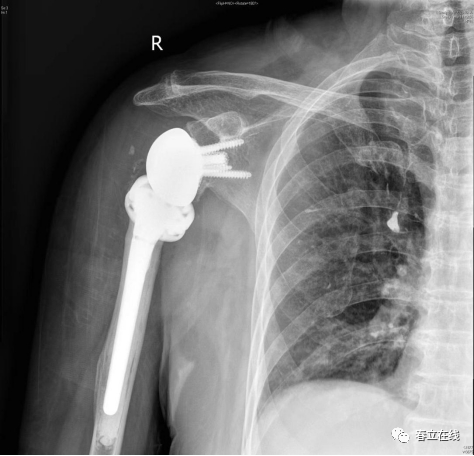

【优选病例】反置式人工全肩关节置换术病例分享

患者1年前无明显诱因下感右肩部疼痛,右肩关节活动受限,曾至当地医院就诊后,行肩关节KI示:右肩袖损伤,右肩关节粘连性肩关节囊炎,右肩关节退变,右侧肩关节积液,予以保守治疗,现感疼痛持续,为求进一步诊治,遂至我院门诊就诊,门诊拟“右侧肩关节骨性关节病+巨大肩袖撕裂“。

该例手术是南通大学附属医院骨科主任王友华教授团队成功为患有右肩关节骨性关节炎的范奶奶实施反置式人工全肩关节置换术术中出血少、创伤小术后范奶奶右肩疼痛消失经过康复训练后手臂可自如活动。

术中片